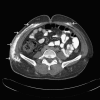

Dermatomyositis with extensive calcification in an adult

This report reviews a case of dermatomyositis presenting with weakness and extensive calcification in an adult. While dermatomyositis is not uncommon in adults, it is uncommon for calcifications to be present. Children develop calcifications more frequently than adults. When present in adults, small calcifications on areas of frequent trauma such as elbows and fingers are more common. However, this patient presented with large calcified deposits in his abdomen and extremities. His treatment and course are described.